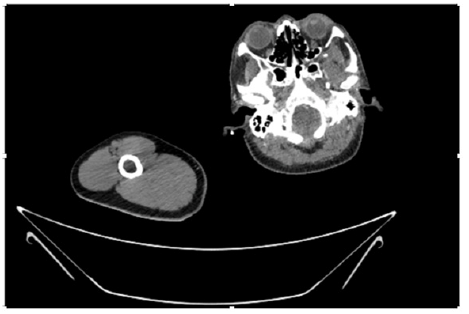

55-years-old chronic smoker had acute, severe pain in the right upper limb for one week; it was cold upto mid arm with skin discoloration. He also noticed numbness and weakness of movement of elbow joint. He underwent below elbow amputation in February 2023 for acute ischemia of left upper limb. He was a current chronic smoker; 15 pack year. General condition was weak; temperature was normal; blood pressure was 100/60mmHg; heart rate was 92/minutes with sinus rhythm; SpO2 was 97% on air; heart was normal. In lower extremities, all peripheral pulses were intact. Local Examination of right upper limb revealed as follows: tenderness; coldness; discoloration; decreased motor function and sensory modalities. Axillary, brachial and radial pulses were not palpable. Hand-held Doppler failed to detect any signal in arterial system; therefore, we arranged for emergency embolectomy. complete occlusion of right upper limb arterial system Full blood count showed high hemoglobin (14.6gm%); normal total WBC and platelet count. Coagulation profile was normal. Parenteral unfractionated heparin, antibiotics, tramadol, proton-pump inhibitors, anti-platelets and HMG CoA reductase inhibitors were given. Doppler ultrasound demonstrated complete occlusion of right upper limb arterial system. CT Angiogram illustrated occlusion of subclavian artery downwards on both sides. Figures 1-14 shows complete occlusion of right subclavian artery without collaterals. On Day ‘2’ of admission, the patient passed black tarry stool for 3 times. However, the vital signs were stable; blood pressure was 100/60mmHg; heart rate was 92/min; SpO2 was 97% on air; the abdomen was soft and not tender. Above elbow amputation was done on Day ‘2’ of admission. Intra-operative findings were as follows: (1) no active bleeding at brachial artery; (2) thrombosis along brachial artery; (3) muscle color and consistency were not healthy.

Figure 4: CT Angiogram at neck showing normal brachio-cephalic trunk, common carotid artery, and narrow right subclavian artery.

Figure 5: CT Angiogram at neck showing normal brachio-cephalic trunk, common carotid artery, and narrow right subclavian artery.

Figure 6: CT Angiogram at neck showing brachio-cephalic trunk, common carotid artery and narrow right subclavian artery.

Figure 7: CT Angiogram at neck showing brachio-cephalic trunk, common carotid artery and narrow right subclavian artery.

Figure 10: CT Angiogram at upper arm showing totally occluded right axillary artery; normal internal carotid artery and external carotid artery.